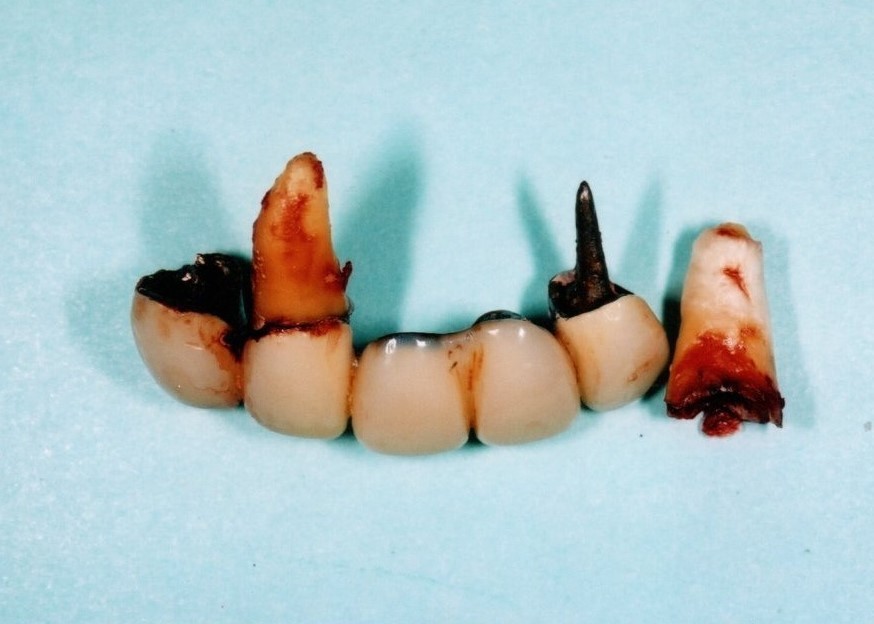

ブリッジの欠点

少ない本数の土台で支えるブリッジの場合、過重負担のため、支える歯がむし歯や歯槽膿漏で悪くなると、ブリッジ全て失う可能性があります。

特に保険で作られた適合があまいブリッジは約7年で50%が悪くなります。

少ない本数で支えられ作られたブリッジ、見た目はよいですが…

少ない支えで過重負担となり、支える歯ごと抜けてしまいました。

その結果、多数の歯を一度に失うことになりました。